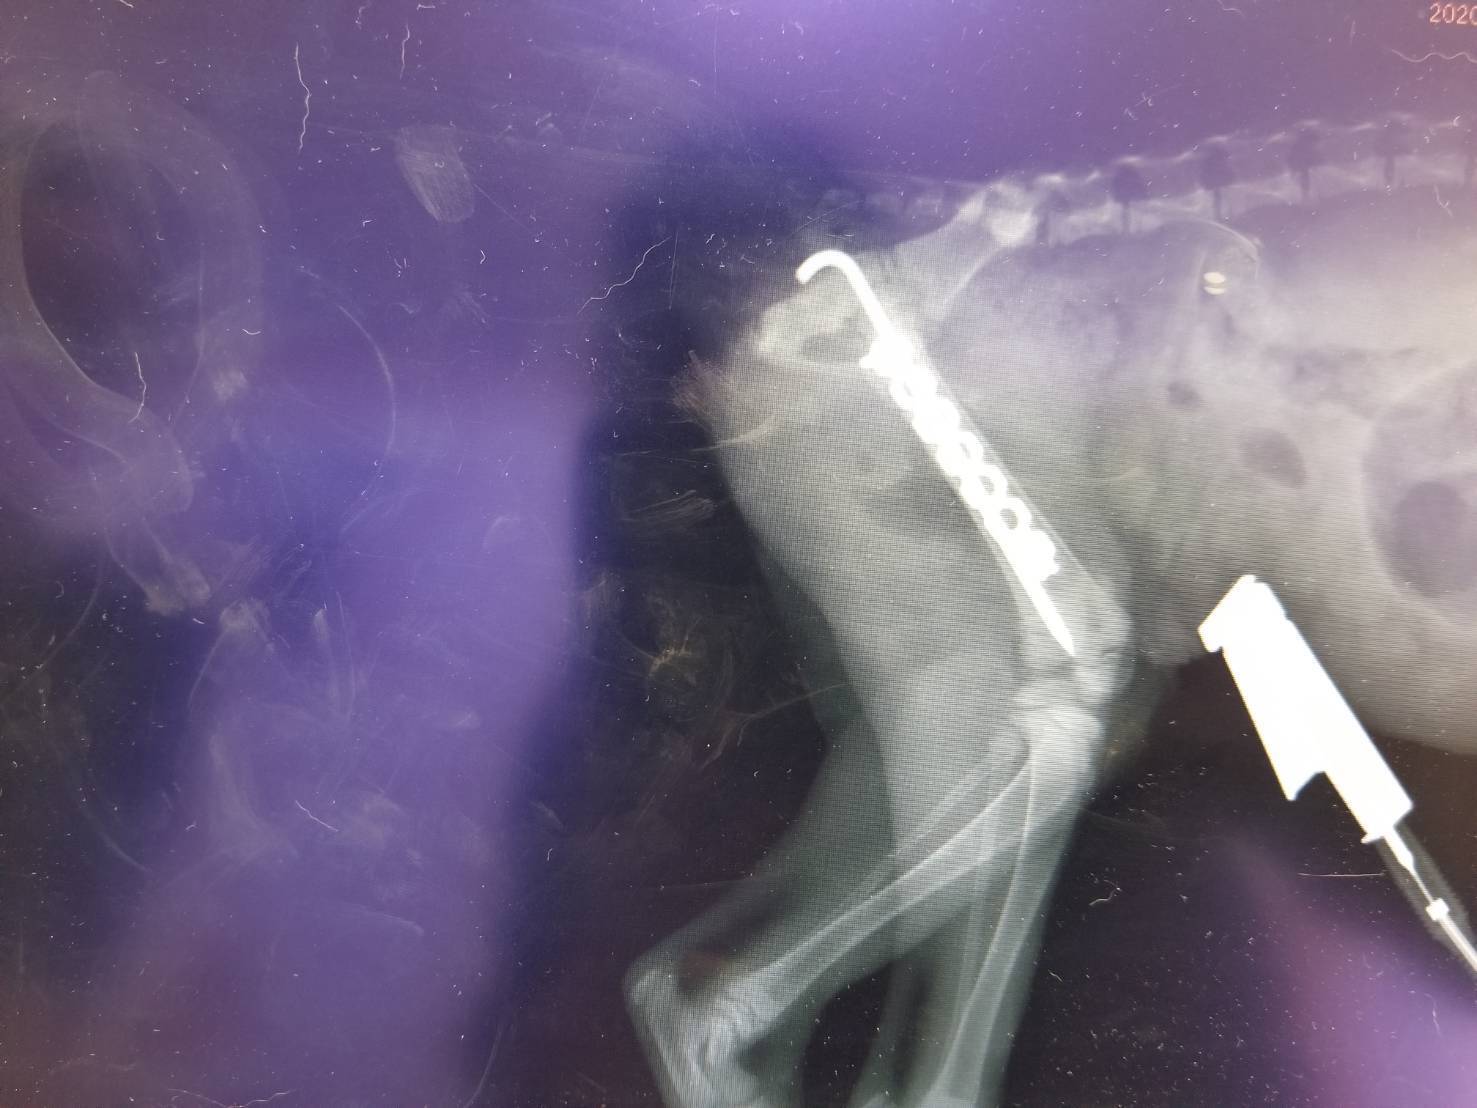

本日、無事骨折部位にピンを入れる手術に成功いたしました!7mmしか後ろ足の骨の太さがなかったらしく先生にもかなり頑張っていただき感謝の限りです!

今後の予定に関してですが、回復を見て再度埋め込んだピンやプレートを外す手術を行うとのことです。